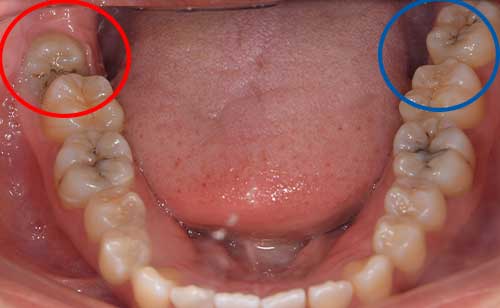

上顎はしっかり親知らずがはえています。下顎は右側は(青色)しっかりはえていますが、虫歯になっています。下顎の左側(赤色)は斜めにはえています。またこちらも虫歯になっています。

麻布十番歯科の虫歯になっている親知らずと斜めに生えた親知らずの症例イメージ